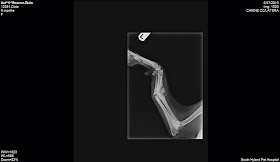

| x-ray before |

This

is a nasty break. She's lyme positive and scabies too.Dixie's leg surgery was 1 1/2 hours long by a board certified surgeon. He got her leg

straightened our almost 100%!

She should do really well. I would estimate her now at 1 1/2 yrs old. Dr. Murphy did an amazing job and I followed up doing the spay.